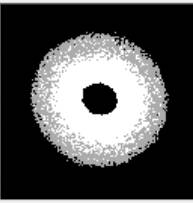

У роботі представлено результат експериментальних досліджень

параметра деформованості еритроцитів із захворюваннями крові, а саме хронічний

мієлолейкоз та нормобластна анемія. В основу експериментальних досліджень було

покладено аналіз дифракційних картин мазків крові, які були отримані при

проходженні лазерного випромінювання довжиною хвилі 635 нм (рис.1).

а) б)

Рис.1. ДК венозної крові: а) здорової людини; б) з патологіями.